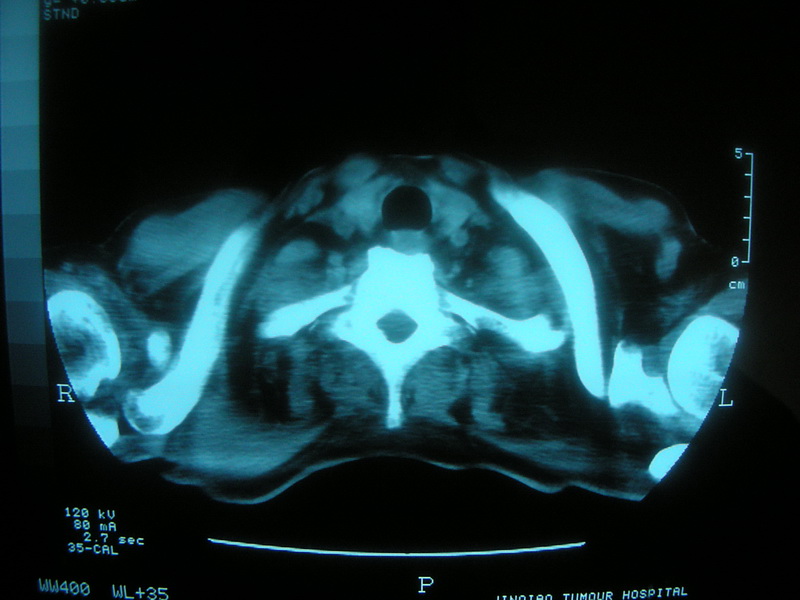

标题: CT11692:男,63岁,糖尿病史15年.抗炎治疗7天,病情 [打印本页]

标题: CT11692:男,63岁,糖尿病史15年.抗炎治疗7天,病情

请老师看看是结核还是炎症?